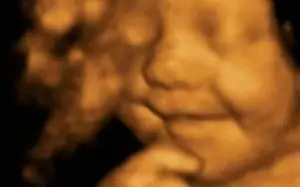

The Smiler Вы знаете ту песню Фаррелла «Happy», под которую все танцевали на премии «Грэмми»? Этот малыш чувствует счастье еще до рождения. Малыш Лео был

фигурирует в статье в The Telegraph, потому что его широкая улыбка на этой 4D-ультразвуковой фотографии привлекла внимание модельных компаний.